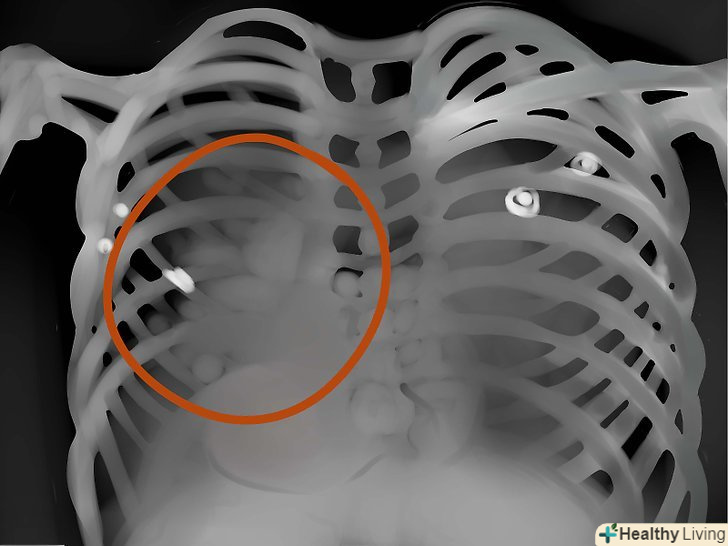

Кістки. уважно подивіться, чи немає де пошкоджень і травм кісток. Розмір, форму, контур і колір кісток необхідно примітити - все це цінний діагностичний матеріал, на підставі аналізу якого можна виявити безліч захворювань і патологій.

Області легенів.оцініть симетричність, васкулярність, наявність сторонніх мас, вузликів, інфільтрату, рідини і т.д. якщо в легкому слиз, кров, гній, пухлина або щось ще-то ця область буде яскравіше, а інтерстиціальні позначки - менш помітні.

Коріння легенів. зверніть увагу на ці області і подивіться, чи немає там якихось вузлів, силуетів і т.д. на фронтальному вигляді більшість тіней в області коренів-це ліва і права легеневі артерії. Ліва завжди вище правої. Пошукайте окальциневшіе лімфатичні вузли в області коренів-це можуть бути сліди туберкульозу.